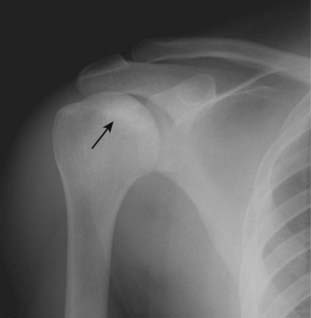

image Multiple myeloma, the most common primary malignancy of bone in adults, can occur in a solitary form, often seen as a soap-bubbly, expansile lesion in the spine or pelvis (called a solitary plasmacytoma), or a disseminated form with multiple, punched-out lytic lesions throughout the axial and proximal appendicular skeleton.

image Plasmacytomas appear as expansile, septated lesions, frequently with associated soft tissue masses (Fig. 21-23).

image

Figure 21-23 Solitary plasmacytoma, shoulder.

There is a lytic lesion in the proximal humerus (solid black arrow), which destroys the cortex (dotted black arrow) and contains multiple septations (solid white arrow). This is the so-called soap-bubbly appearance and can be seen with expansile metastases and solitary plasmacytomas, a precursor to the more disseminated form of multiple myeloma.